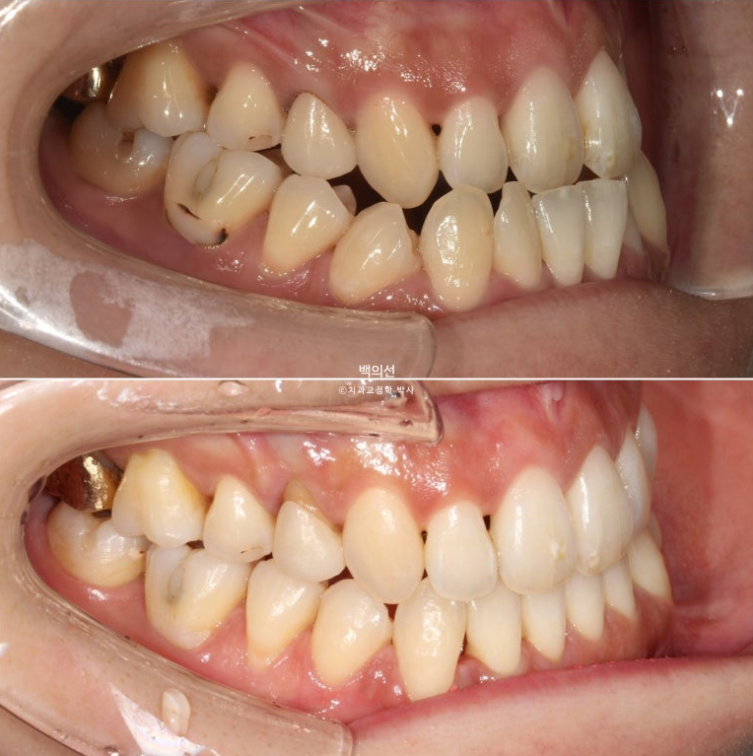

앞니뿐만 아니라 큰어금니까지 반대교합입니다.

앞니 중심선은 약 2mm 어긋나 있습니다.

어금니 역시 심한 3급 교합관계를 보입니다. 앞니는 반대교합으로 거꾸로 물립니다.

24.01~25.07

앞니 뿐만 아니라 어금니 반대교합도 함께 개선되었습니다.

중심선은 개선되었습니다.